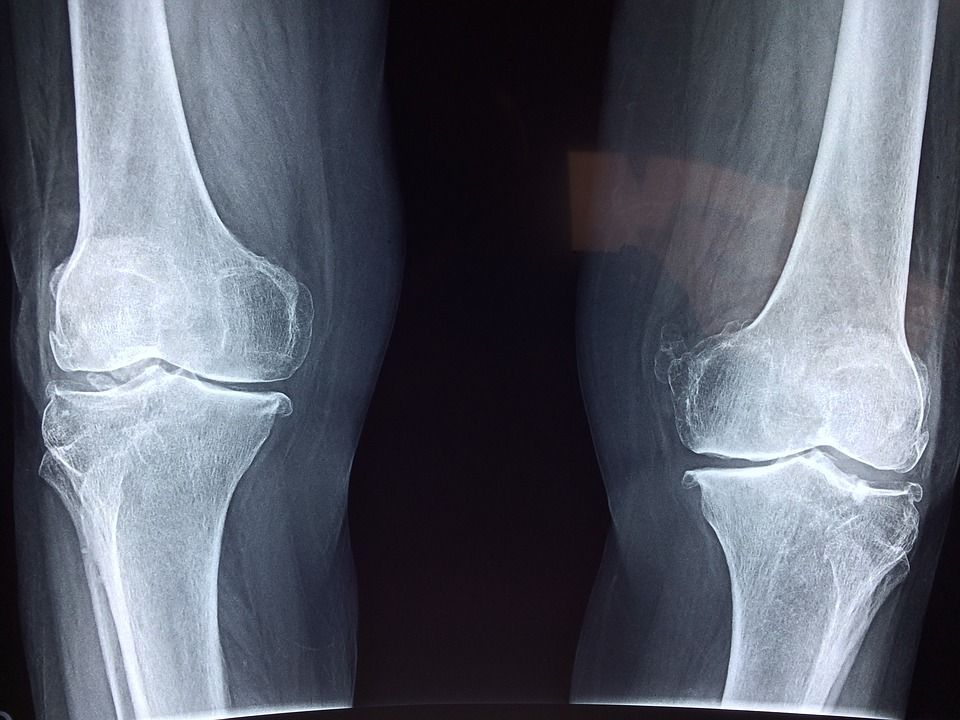

Il 20 ottobre è la Giornata mondiale dell’osteoporosi e per questa occasione facciamo il punto della situazione sulla fragilità ossea, la forma più grave di osteoporosi, che in Italia causa 250 mila fratture di femore all’anno. Si tratta di un trauma non solo fisico ma che ha degli effetti anche per la psiche di chi soffre di questa patologia, che colpisce soprattutto le donne, e dei familiari. Dolore cronico, ridotta capacità motoria e depressione sono soltanto alcune delle complicazioni che abbassano la qualità di vita dei malati e di chi se ne prende cura.

Il 63% delle donne che hanno avuto una frattura di femore – avvertono gli esperti – ha già riportato anche fratture vertebrali, molto spesso scambiate per un banale mal di schiena dovuto all’età. Le fratture vertebrali sono invece le più diffuse complicanze dell’osteoporosi e rappresentano l’inizio della ‘cascata fratturativa’: il 25% dei pazienti, uno su 4, riporta una seconda frattura vertebrale entro un anno, e il rischio di frattura femorale quadruplica.